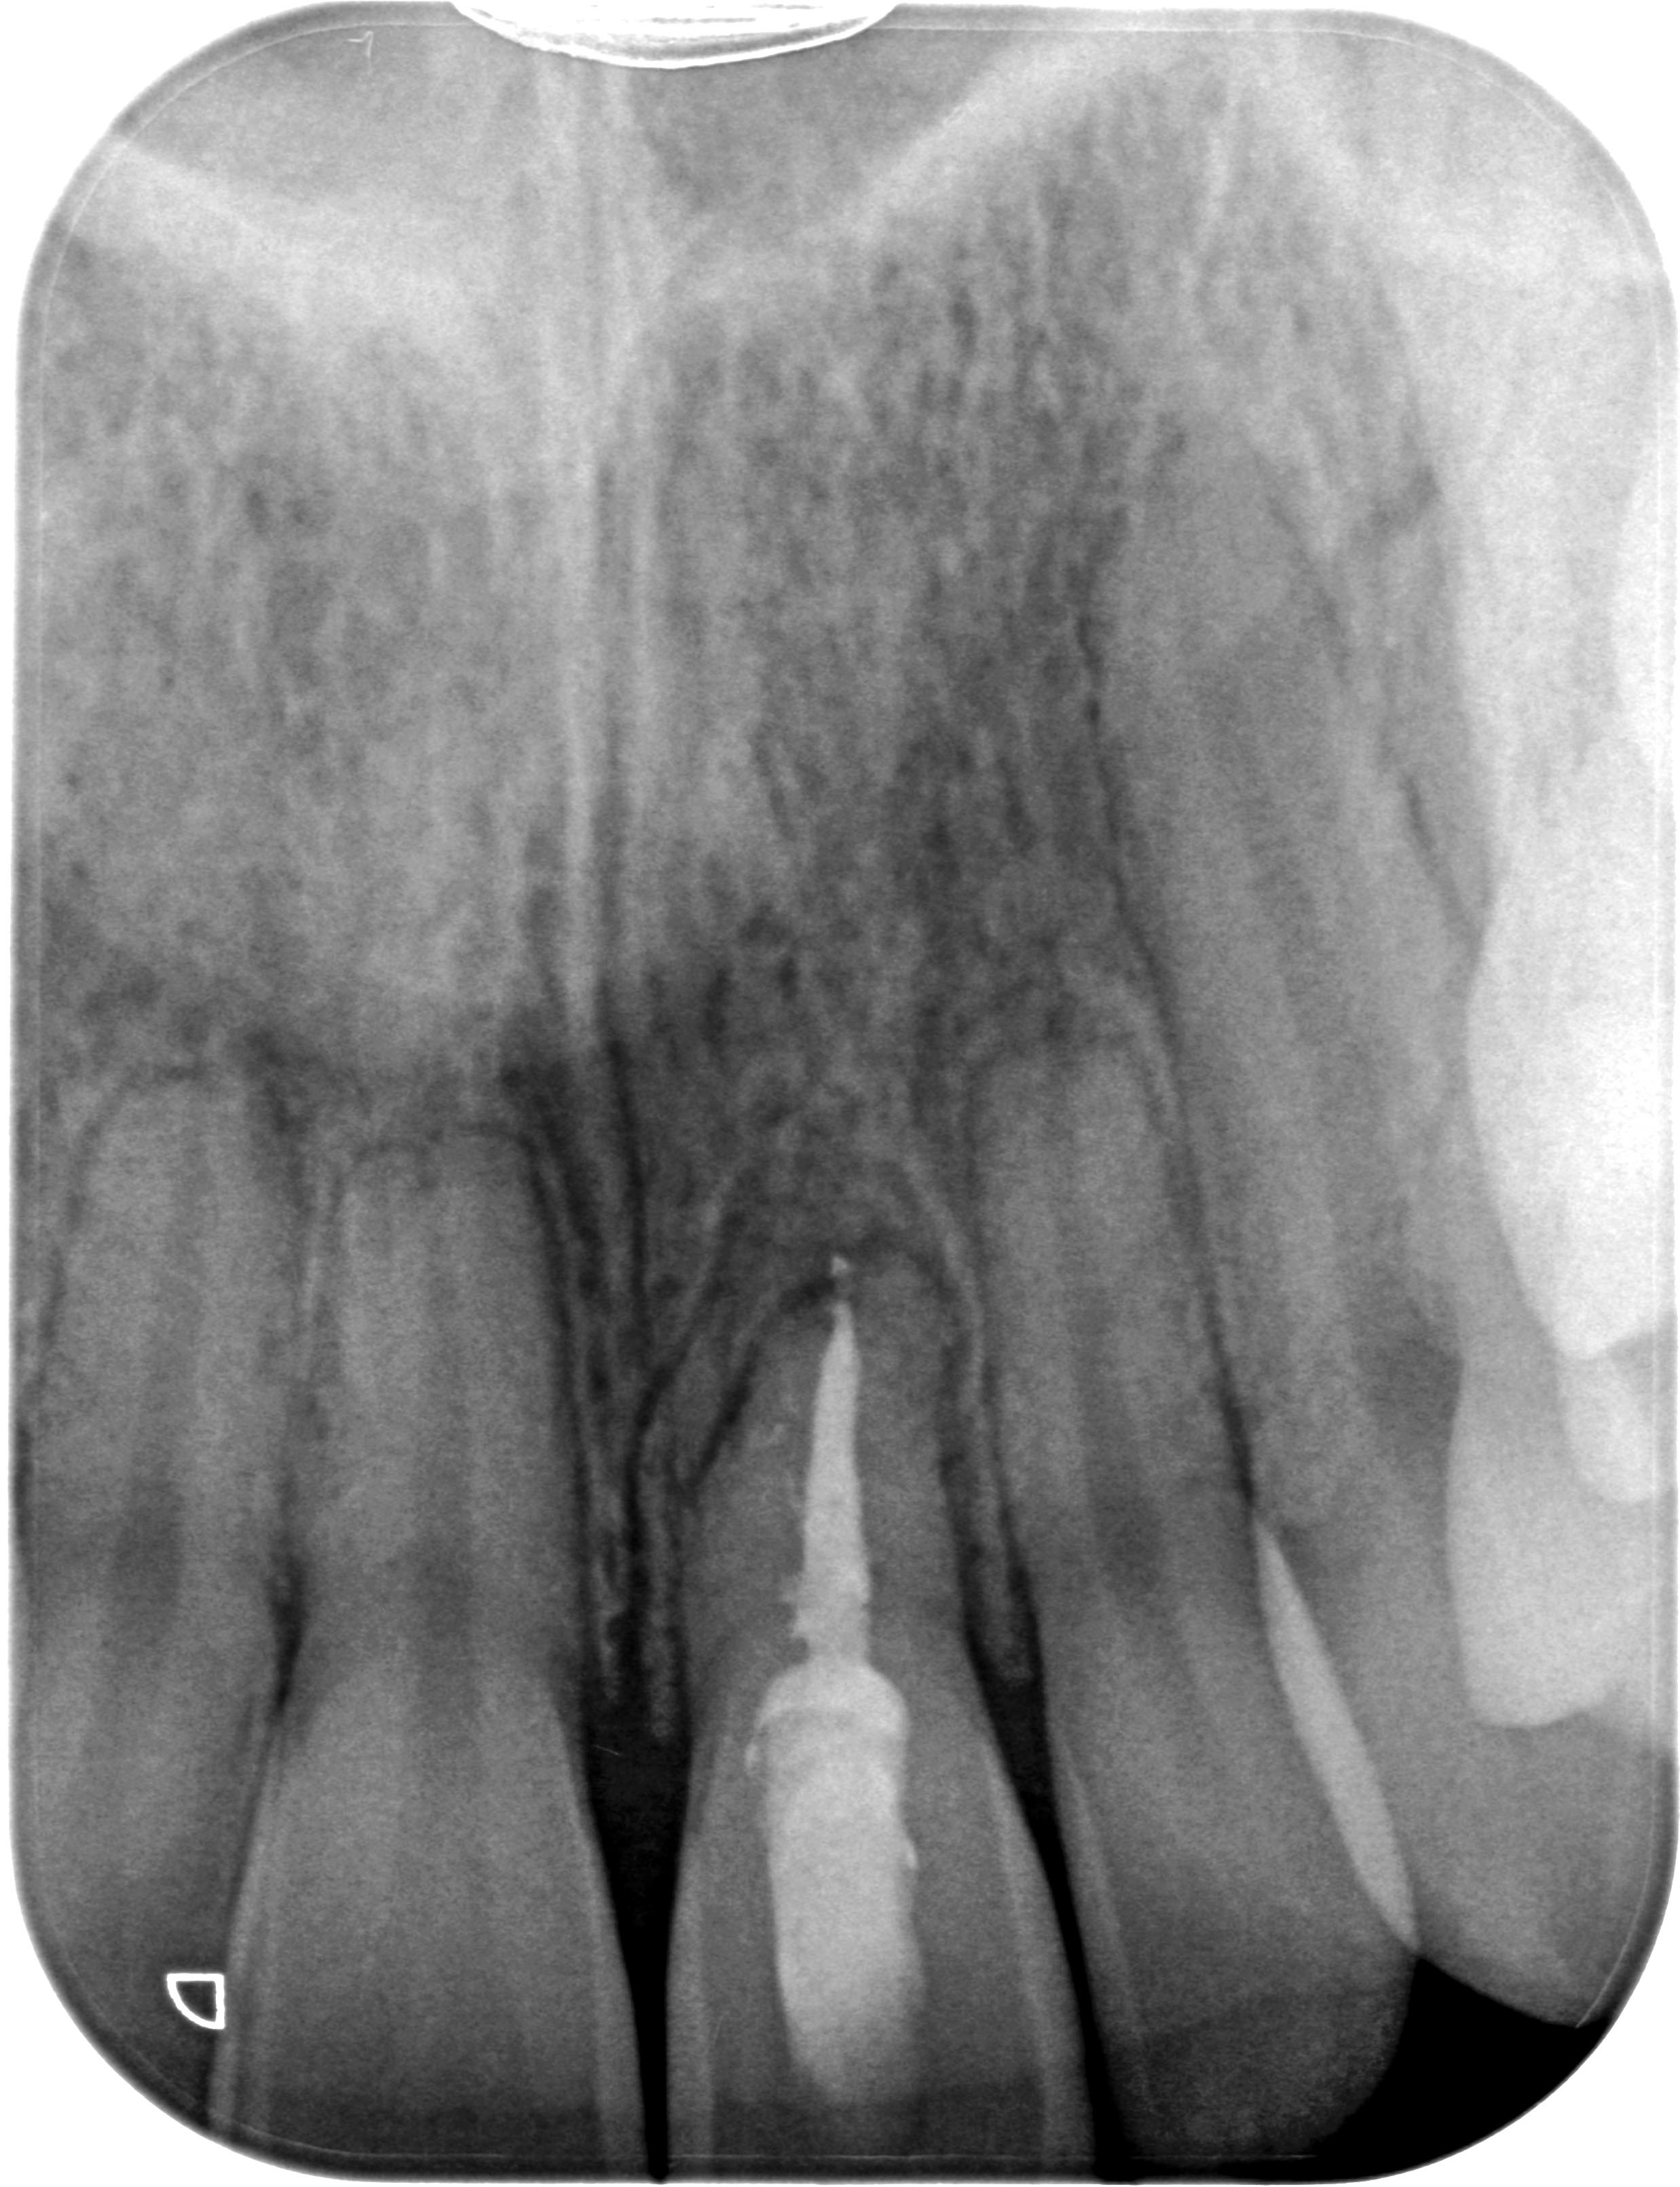

SL21_post_WF-1 Veröffentlicht 16. Dezember 2013 am 2475 × 3222 in Hoffnungsloser Frontzahn – Lockerungsgrad 3 – Die Fortsetzung